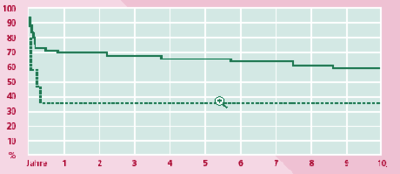

Alle Patienten erhielten postoperativ eine therapeutische Antikoagulation mittels Heparin mit einer später durchgeführten "Marcumarisierung". Die lebertransplantierten Patienten erhielten eine Standardimmunsuppression, die sich nicht von der anderer lebertransplantierter Patienten unterschieden hat. Postoperative Komplikationen bestanden in der Mehrzahl in septischen Problemen bis zum Mehrfachorganversagen. Von den 65 Patienten haben bis heute 36 Patienten überlebt. Die 10 Jahres- Überlebensrate beträgt nach Lebertransplantation insgesamt 58%, bei alleiniger Lebertransplantation sogar 80% und nach alleiniger Shuntoperation 32% (ABB. 1).